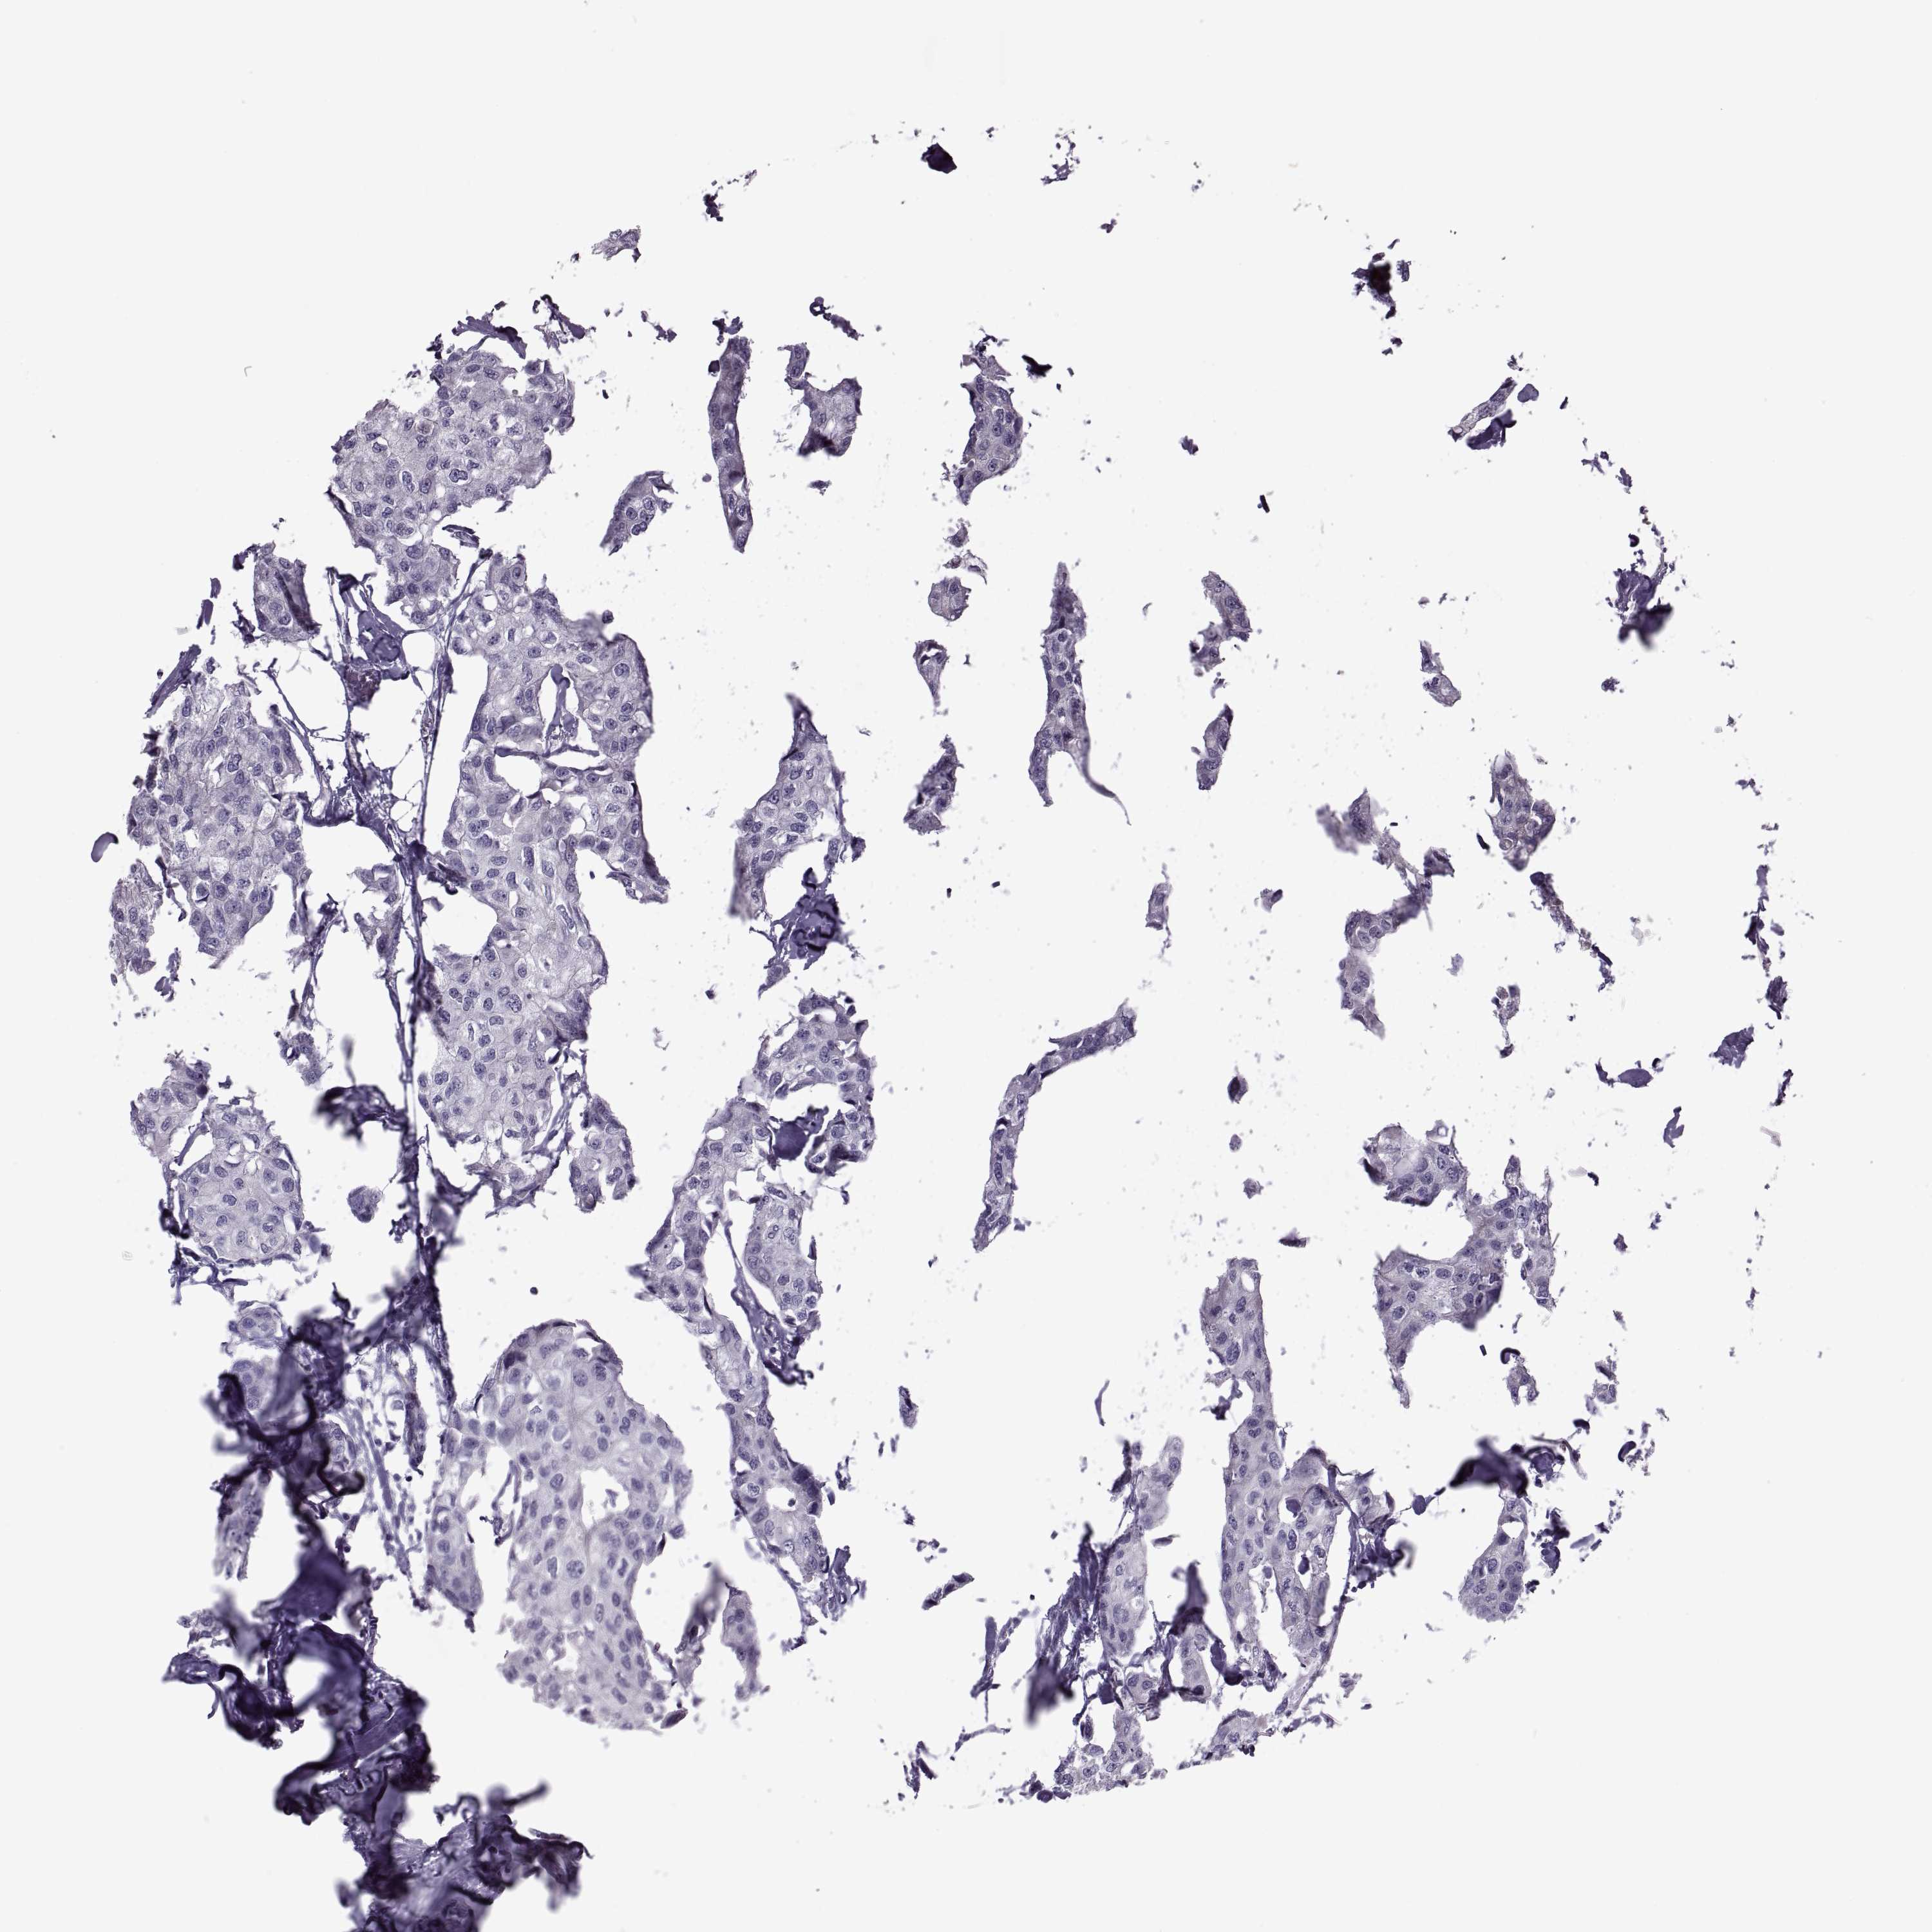

BRCA TCGA BRCA VALIDATION PROTEIN EXPRESSION